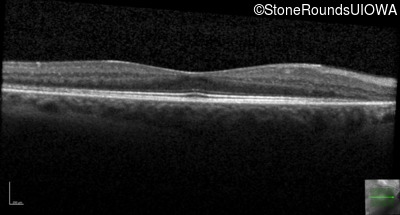

Optical Coherence Tomography - Left - 20/25 -1 sc

Exemplar / OCT Stack

OCT Stack